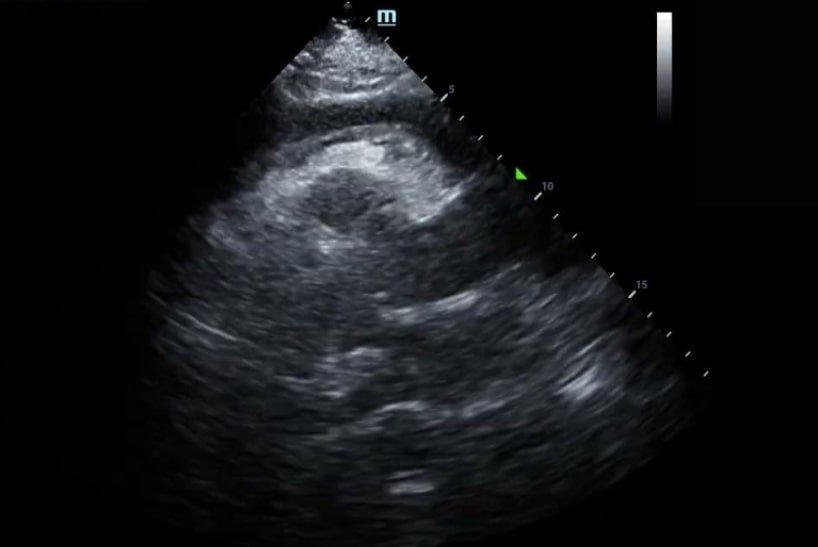

When asked to lie flat for the cardiac exam, he noted worsening chest discomfort. Upon obtaining the initial Parasternal Long Axis (PLAX) view, all eyes in the room grew wide in surprise.

Here you can see a significant pericardial effusion in PLAX and Subxiphoid views with concerns for early tamponade. This was communicated with the cardiology team who promptly drained 400cc of serosanguinous fluid. Ultimately there was no obvious source for this effusion. Since this experience, I always make sure to take at least a quick peek at the heart in respiratory cases where lung ultrasound is unrevealing.